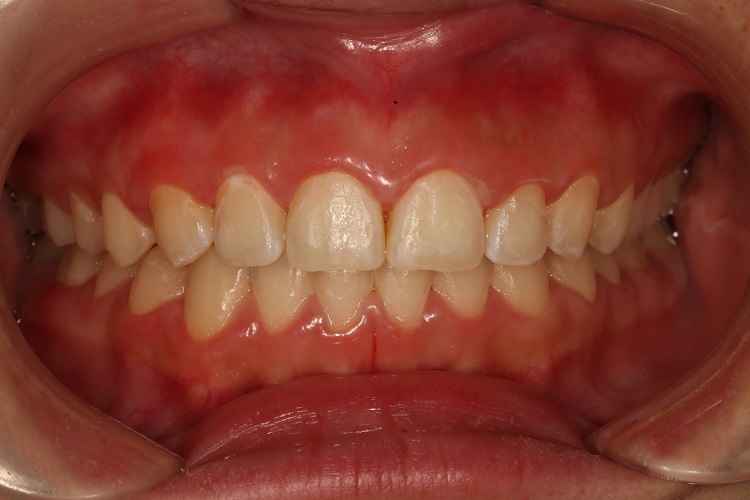

深覆(牙合)可引起不同程度的牙齿前突变形,表现为前牙区表现为上切牙牙轴直立甚至舌倾,上牙覆盖下牙,同时患者嘴巴闭合时可有嘴唇前突,一般呈短方脸形,脸部下1/3高度较短。